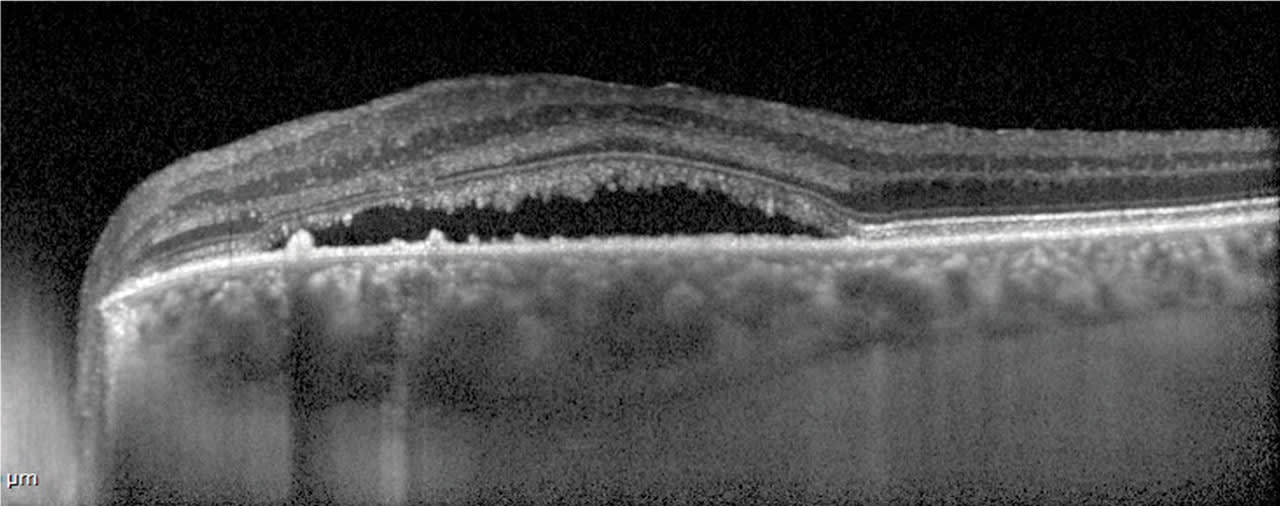

Enhanced depth imaging (EDI) is a scan option on most commercially available OCT systems. It allows for a “deeper” scan, capturing more of the deeper retina and choroidal structures. This technique is useful for any pathology that is in the deeper layers, such as choroidal neovascularization, tumors and choroidal thickness analysis. The scan depth of a typical spectral domain OCT allows for more data of structures from the vitreo-retinal interface to the retinal pigment epithelium. EDI scans adjust for further enhancement of the deeper layers, and provides data from (approximately) the inner plexiform layer to the sclera, resulting in more data resolution of those layers. (Figures 1 and 2)

EDI is a very useful tool in evaluating nevus vs tumor in the choroid, as the posterior edge of a mass is reflective, allowing for more accurate measurements (Figure 3).